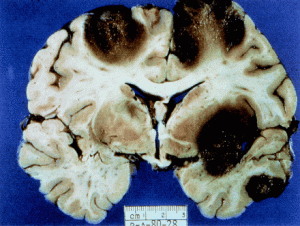

Disseminated infection is caused when a person comes in contact with through an open wound or cut, or through the nostrils. The amoeba then travels through the bloodstream, affecting the skin, lungs and other organs either individually or collectively. When left untreated, much like the locusts above, the Acanthamoeba infects the brain causing a range of symptoms, including Encephalitis, which is a swelling of the brain. Other symptoms are as severe as seizures, loss of senses, and hallucinations. While medical experts don’t understand much about Acanthamoeba affecting the brain and nervous system, we do know if not treated, the resulting disease is often fatal.